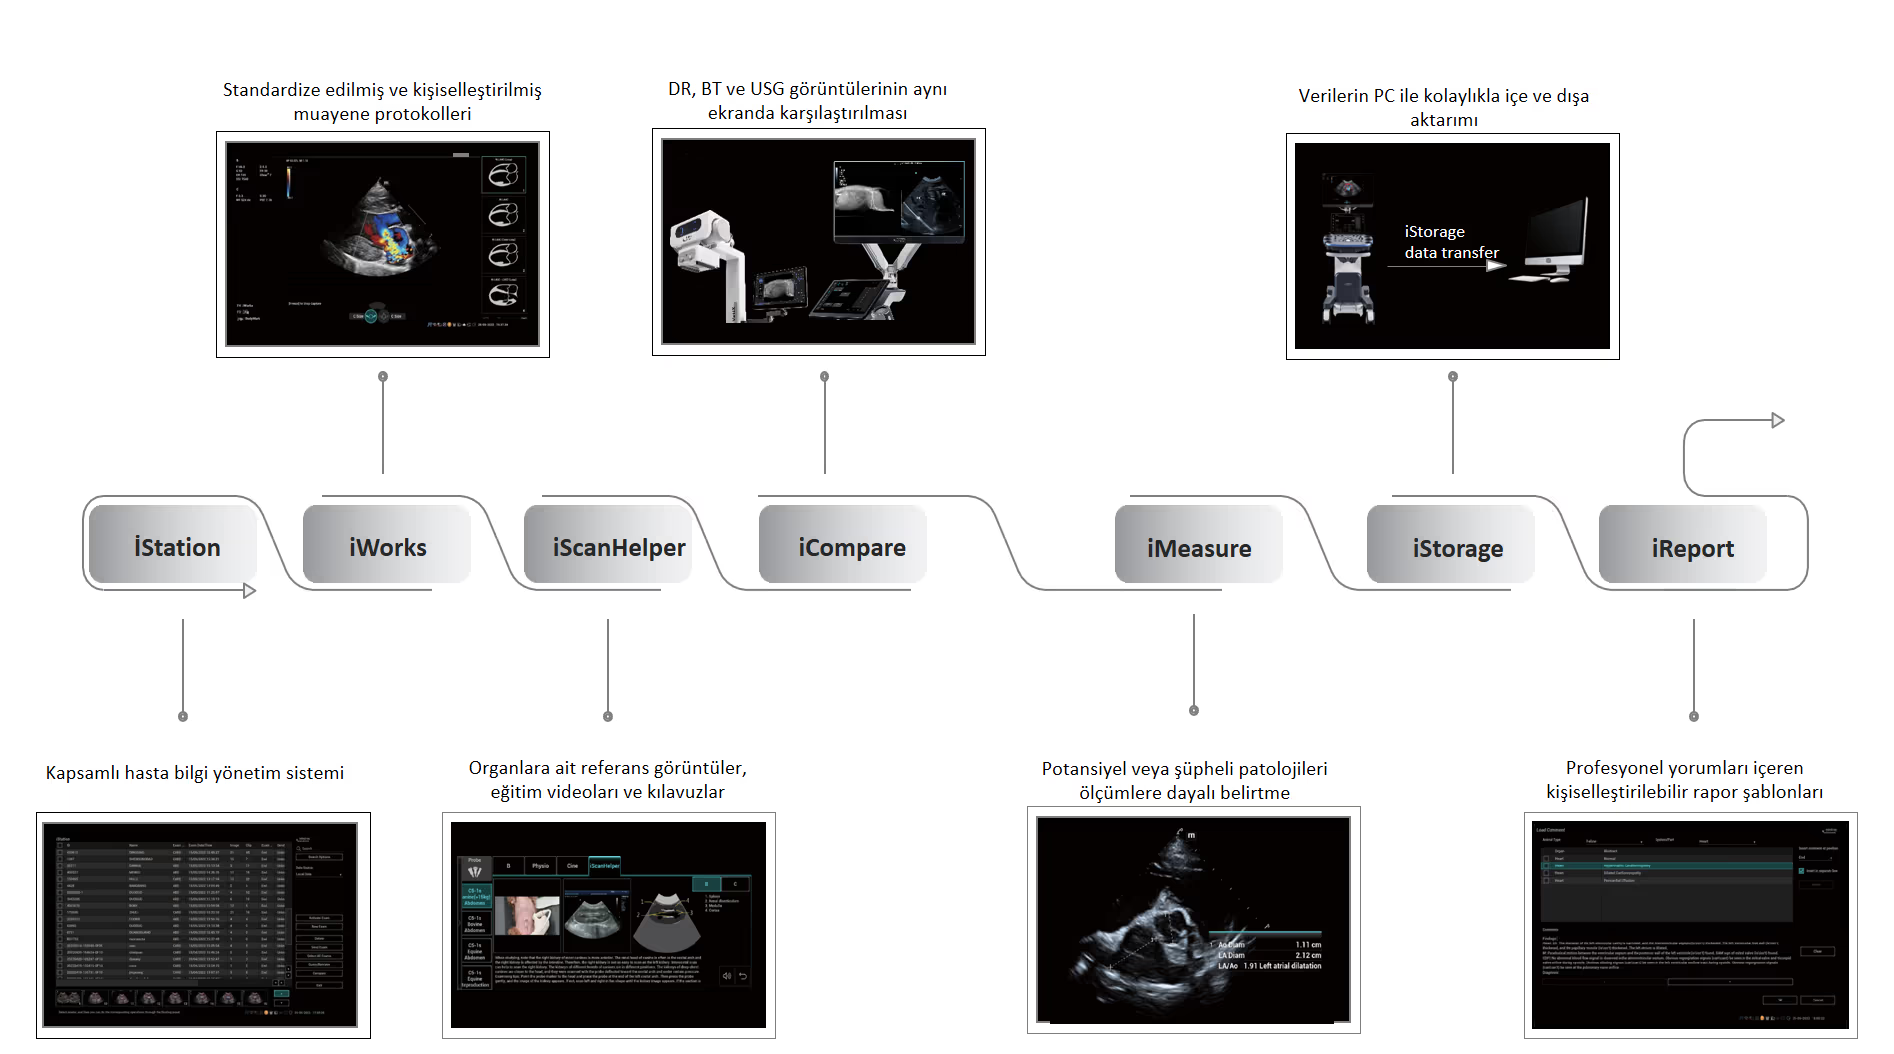

Köpek Böbreği

Köpek Böbreği